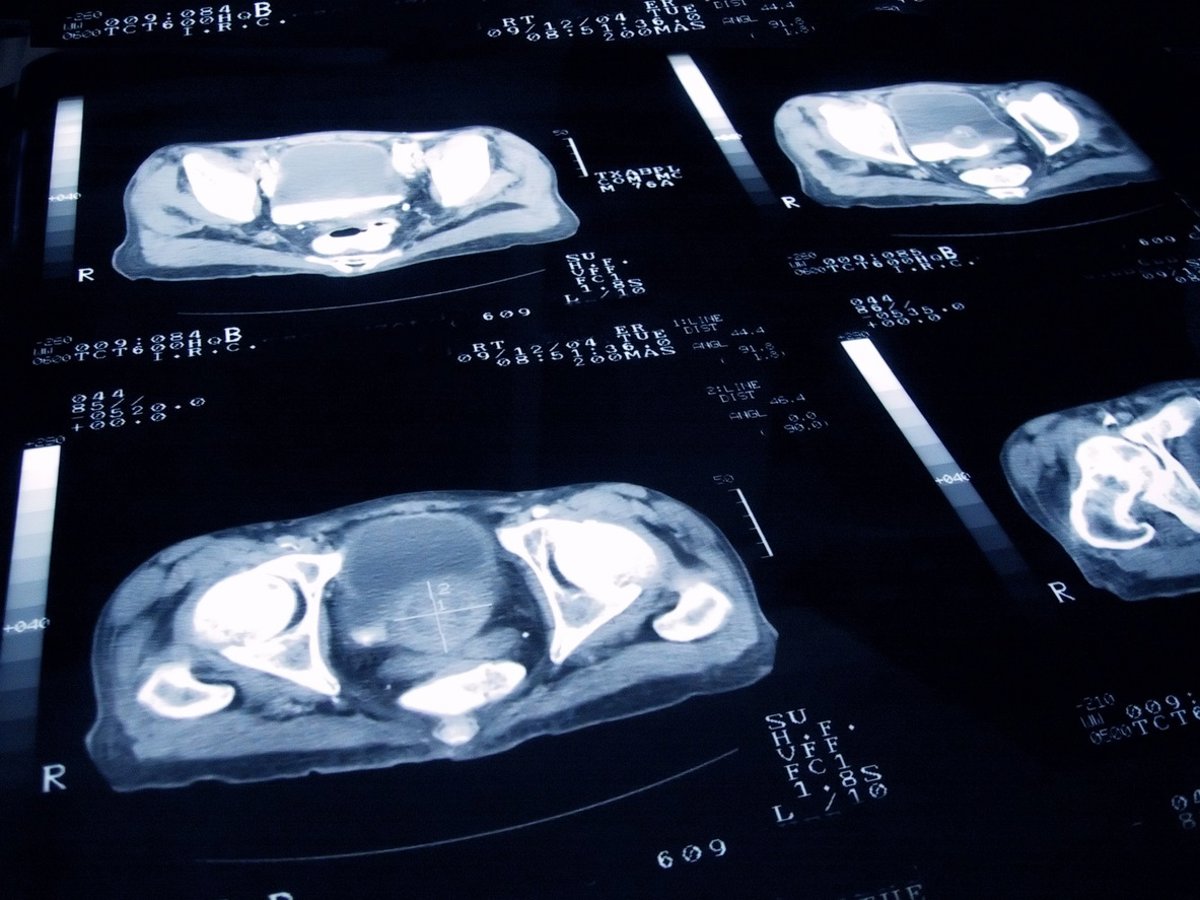

Archivo - Cáncer de próstata

Archivo - Cáncer de próstata - JAMESBENET/ ISTOCK - Archivo